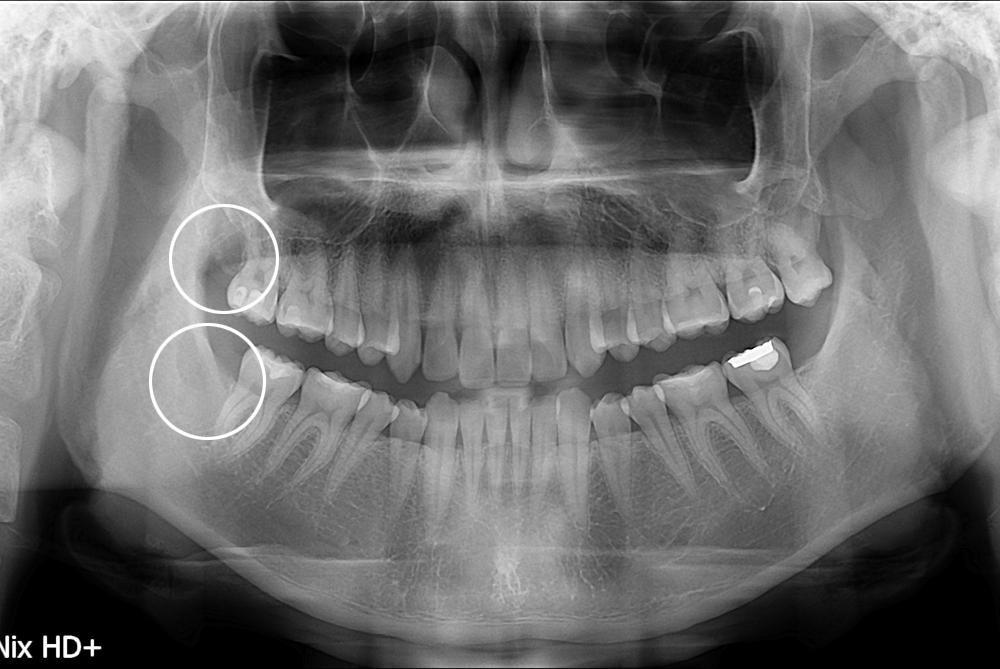

[사랑니] 난발치 사랑니 발치

치료전 : 2017-07-12